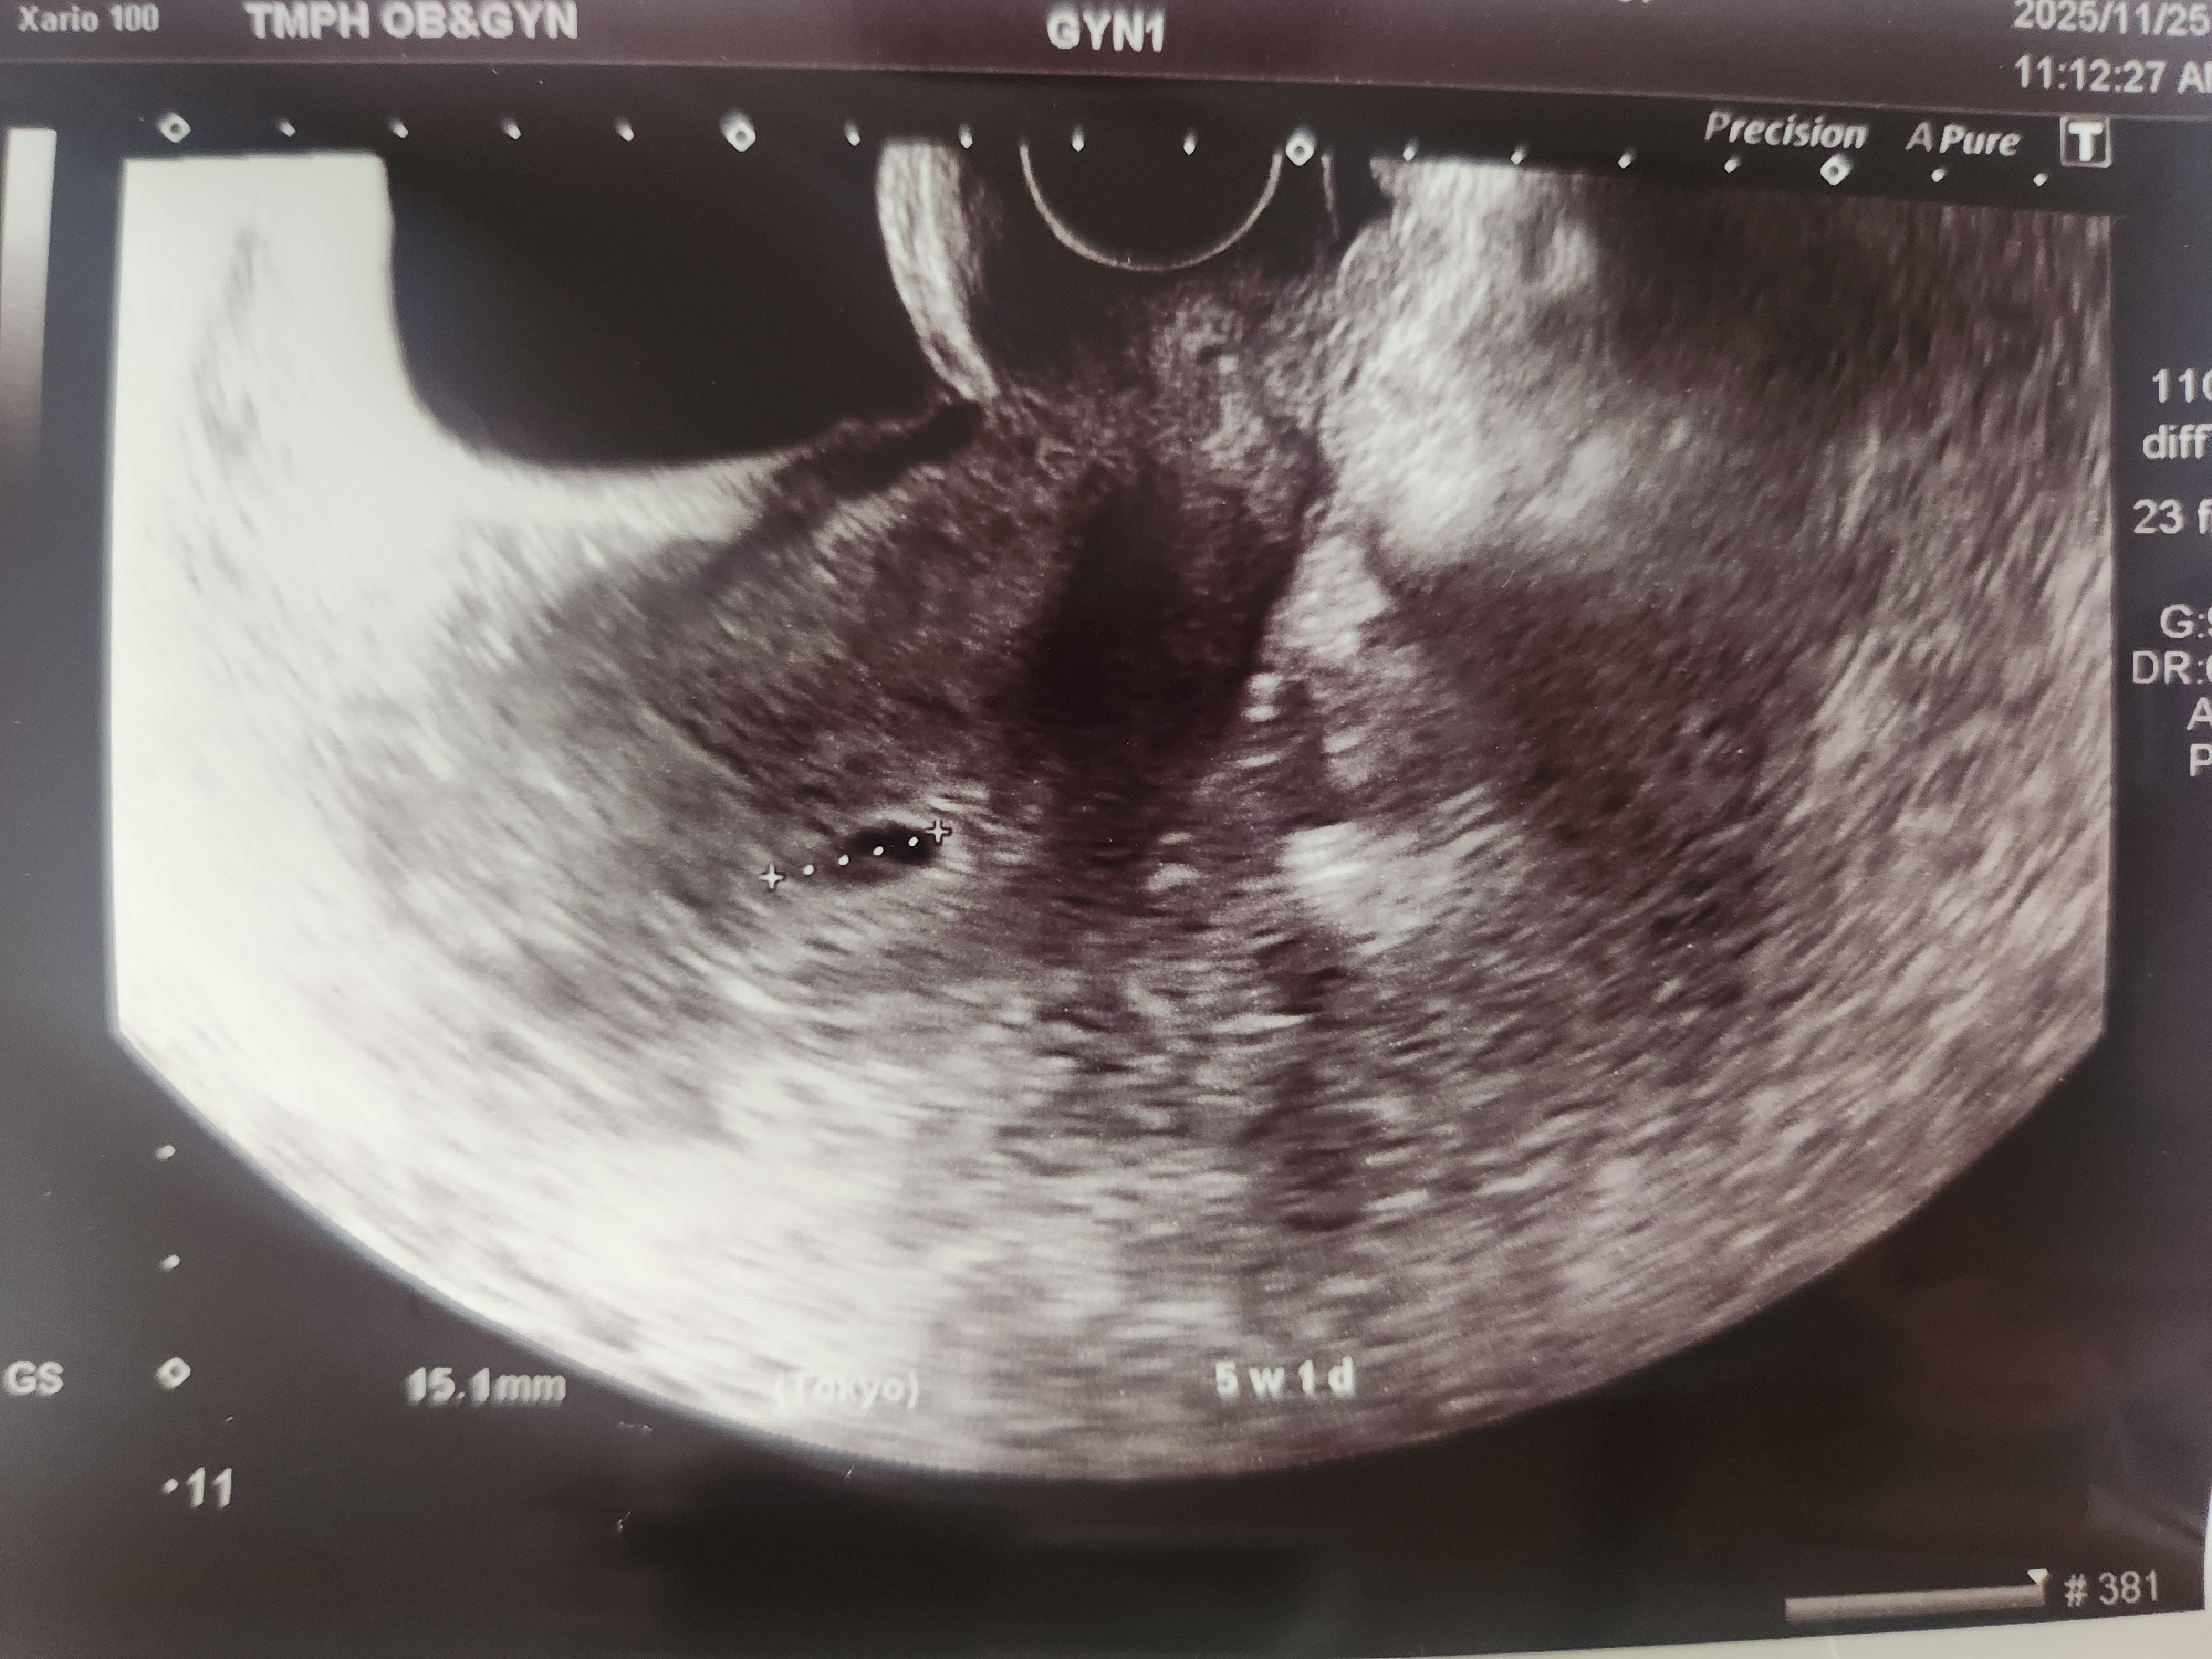

5주차 아기집 보고왔어요

3주차에 임테기 확인하고 2주 기다려서 다녀온건데 아직 너무 작아서 아기집만 겨우 보고왔네요 첫째도 일찍 알아서 첫번째 안보여서 퇴짜 2주후에 가서 작은 아기집에 점같은 아기 처음 확인했었는데.. 처음엔 너무 작아서 아기집이 아기인가 했었어요ㅋㅋㅋ 휴 둘째도 시간 안가는건 똑같네요ㅋㅋㅋ